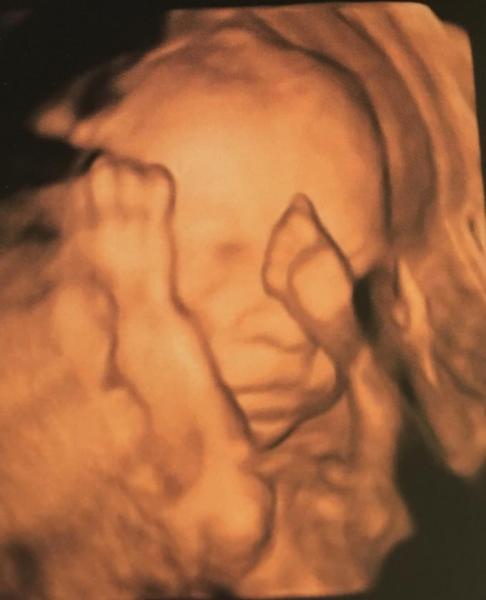

Huhu ihr Lieben War heute bei 26+1 beim FA. Krümel wiegt 870 g und misst 35 cm. GMH stabil, MM unreif, Durchblutung + Fruchtwasser gut. Der doc war zufrieden, aber wenn ich mit euch vergleiche, scheint mir mein Krümel ein Mini zu sein, oder?

Bild zu FA Termin - Forum für August - Mamis